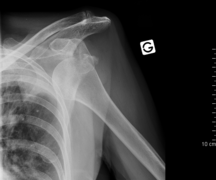

Anterior shoulder dislocation with fracture